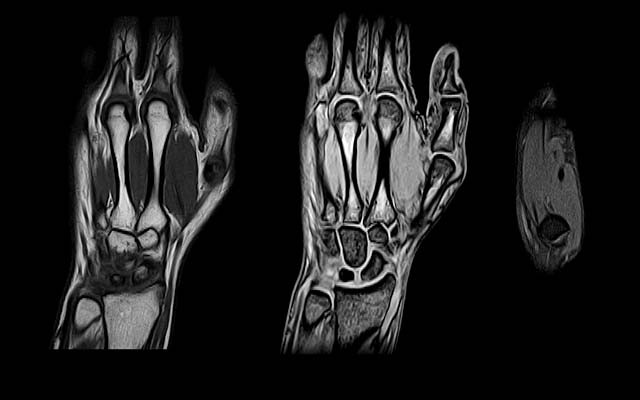

МРТ

Сегодня лучшим визуализационным методом при диагностике ревматоидного артрита является магнитно-резонансная томография (МРТ). Она даёт возможность досконально изучить состояние органов и тканей. Для большинства пациентов процедура проведения МРТ абсолютно безопасна. Тем не менее не всегда можно задействовать этот метод диагностики. Противопоказания к проведению МРТ:

Специальной подготовки к выполнению МРТ никакой не требуется. В общей сложности исследование проходит в течение 45–90 минут. УЗИ и рентгенография значительно уступают этому диагностическому методу по информативности и точности получаемых данных.